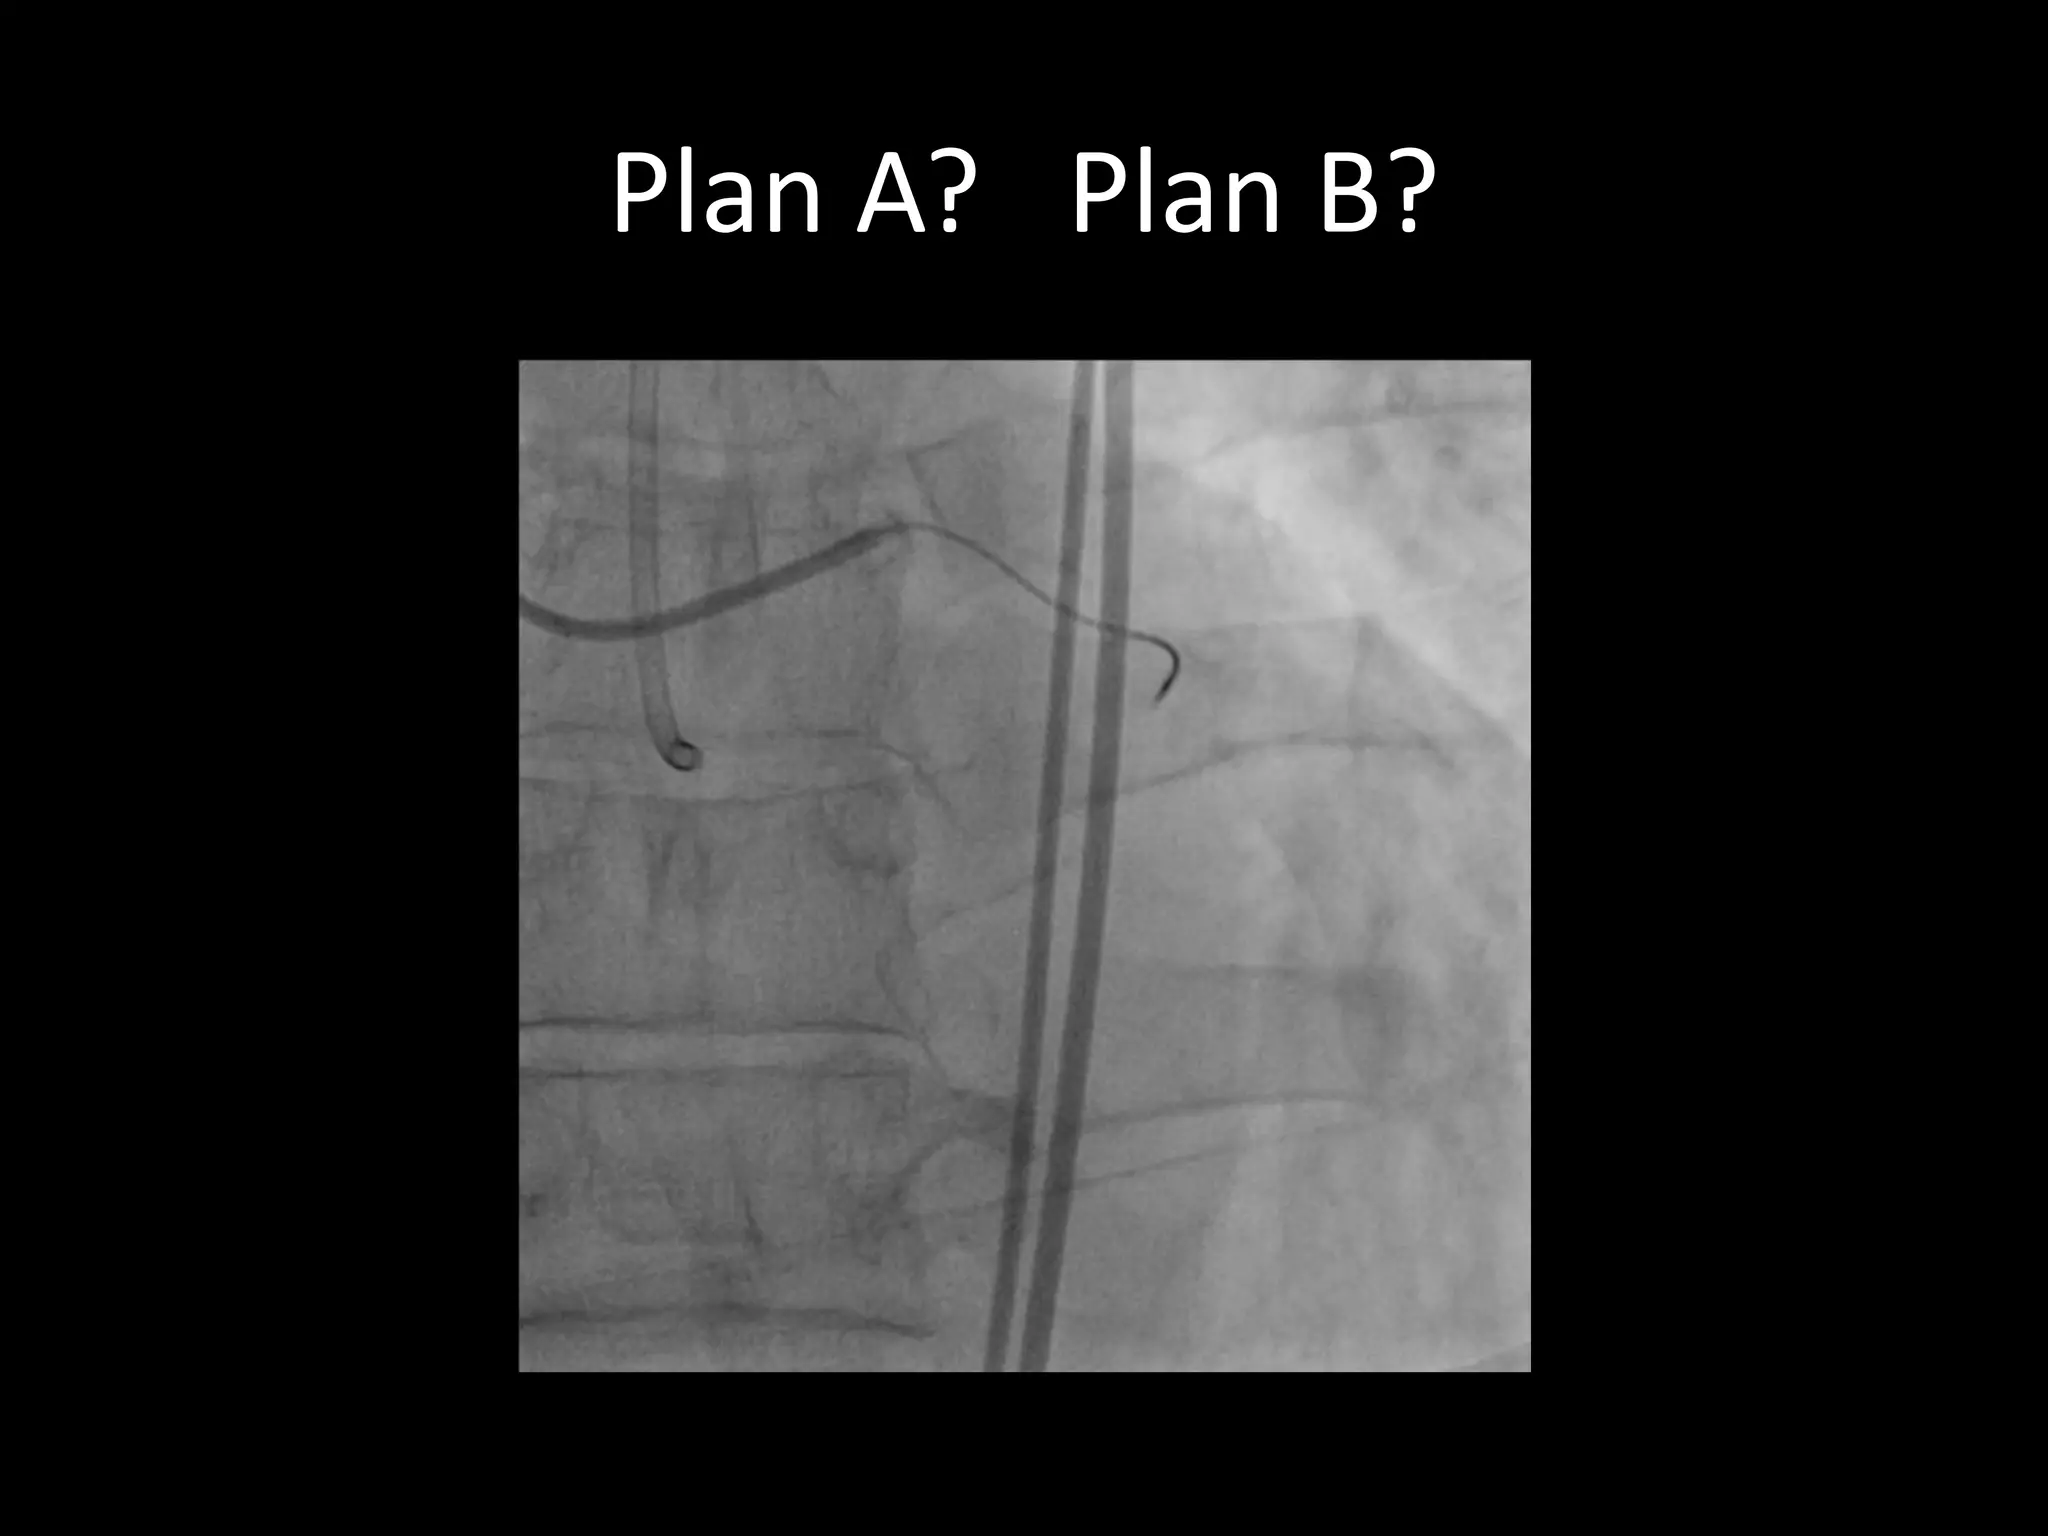

This document provides guidance on evaluating the feasibility of percutaneous coronary intervention (PCI) for a chronic total occlusion (CTO). Key factors to consider include: the patient's tolerance for a long procedure, contrast load, and radiation exposure; the CTO's proximal cap ambiguity, length, distal landing zone, and presence of interventional collaterals; and ensuring good quality angiography. With adequate planning and use of appropriate CTO techniques, feasibility is nearly always present for symptomatic patients. Success rates of CTO-PCI are reported to be 94% when using a planned approach.